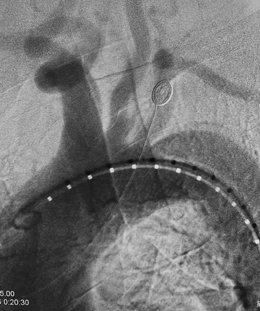

午夜十二点,手术开始,由血管外科贾伟、蒋鹏、程志远三位高年资大夫组成手术团队。介入下,清楚看到患者主动脉破口紧邻左侧锁骨下动脉,如果按照常规手术方案治疗虽然可以挽救病人生命,但必然导致左侧锁骨下动脉闭塞而使左上肢缺血,术中贾伟副主任医师当机立断,决定采用非常规的手术方案:原位体外开窗、保留左锁骨下动脉。虽然手术难度增加了数倍,但是左锁骨下动脉的血流成功保留对病人的意义重大。手术耗时1个多小时顺利结束,凌晨一点半病人转入ICU病房,目前各项生命体征平稳。